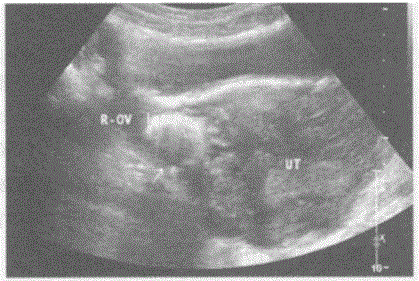

问题 临床资料:女,38岁,自诉放置节育器时腹痛明显,次日后缓解,十年来无明显不适。 超声综合描述:子宫后位,形态大小正常,肌壁回声均匀,宫内膜线居中,内膜厚约1.1cm,宫腔内未见异常回声。子宫角与右卵巢之间可见环状强回声,后伴彗星尾征。 超声提示:

选项 A.卵巢畸胎瘤 B.节育器子宫肌层嵌顿 C.盆腔肠管回声 D.节育器异位

答案 D